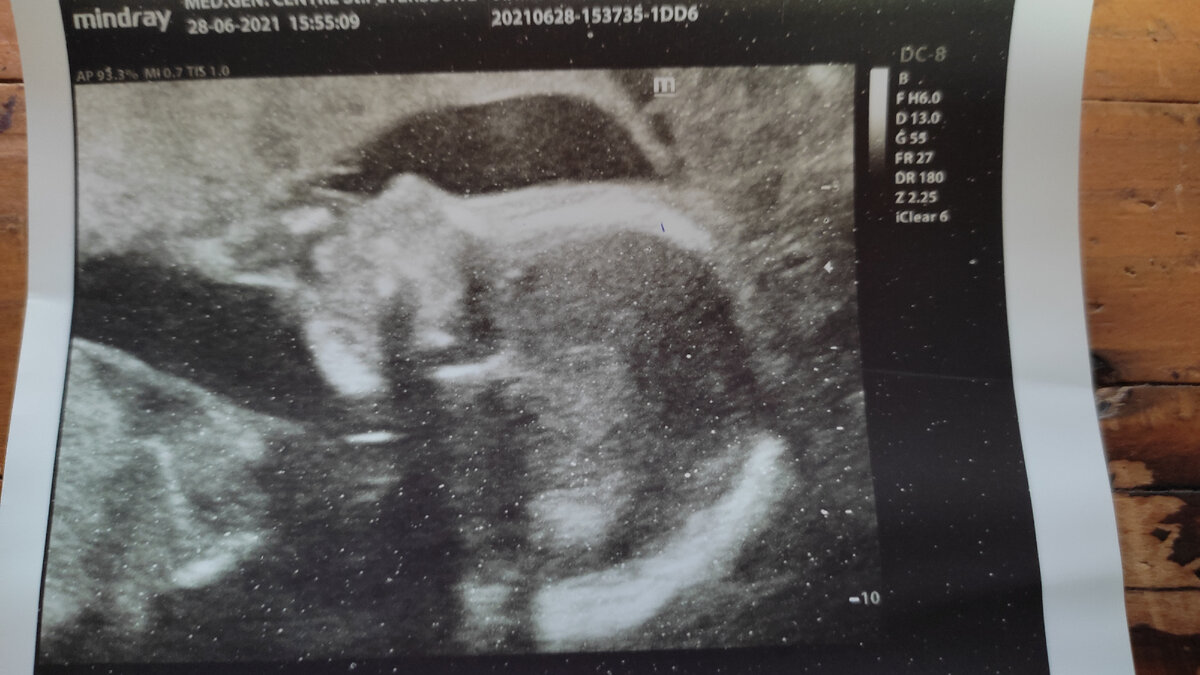

15 ноября 2019 СКРИНИНГ. Мы поехали вместе с Мишей. Конечно мы оба очень переживали. Пришли, сдали документы. Медицинский центр очень большой, красивый, но мне делали бесплатно. Всё, лежу на кушетке, напротив большой экран, и врач начала смотреть нашего малышарика. Я почему то была полностью уверена, что будет девочка, а Миша сказал что будет мальчик. Долго врач смотрела, что то диктовала, медсестра писала, и вдруг говорит, а теперь смотрим на экран, и божечки, там наш малыш, наша мечта к которой мы шли. Конечно слёзы, слёзы счастья. Я попросила записать на диск и сделать фотку.

Врачи очень милые, и пошли на встречу( платно). Сразу сказали, у Вас мальчик. Нет я не расстроилась, я сразу представила как будет счастлив Мишка. Вышла с кабинета, Мишка смотрит на меня с надеждой, и я поцеловав его ,сказала, что будет тебе сын как ты и мечтал. Боже, как он сразу изменился, счастье в глазах. Следующий этап, надо было пойти сдать кровь на патологии. Я честно очень переживала, тряслись руки. Зашла в кабинет, взяли кровь, заполнили анкету. Сказали ждать час, потом результаты. Знаю, что у многих эти анализы готовятся неделю, но там своя лаборатория, поэтому нам повезло. Пошли поели в кафешки, Миша за мной стал ухаживать , я прям видела что он летает от счастья. Но впереди результаты анализа, и я конечно не расслаблялась. Миша был полностью уверен, что всё хорошо. И вот меня вызывают в кабинет.......